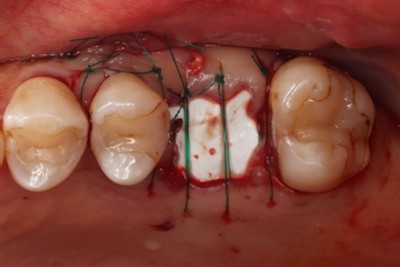

治療中

エムドゲイン®サイトランス®を填入し、レーザーにて血餅形成、縫合

初診時歯周ポケット6mm、左上4番に骨吸収を認める

切開はEPPT(entire papilla preservation technique)

歯周基本治療後に再評価し、ポケットが残存したのでEr:YAGレーザーを併用した歯周組織再生療法(エムドゲイン® 、サイトランス®を使用)を行ったケース

歯周病の好発部位である上顎第一小臼歯近心面における骨吸収に対して再生療法を行ったケース。一般的に根面溝という溝があり歯石の沈着が生じやすい。また溝の存在により術後に歯肉と歯根の付着が生じにくいため、今回はEr:YAGレーザーにて血餅形成を行い組織の安定化を図った。